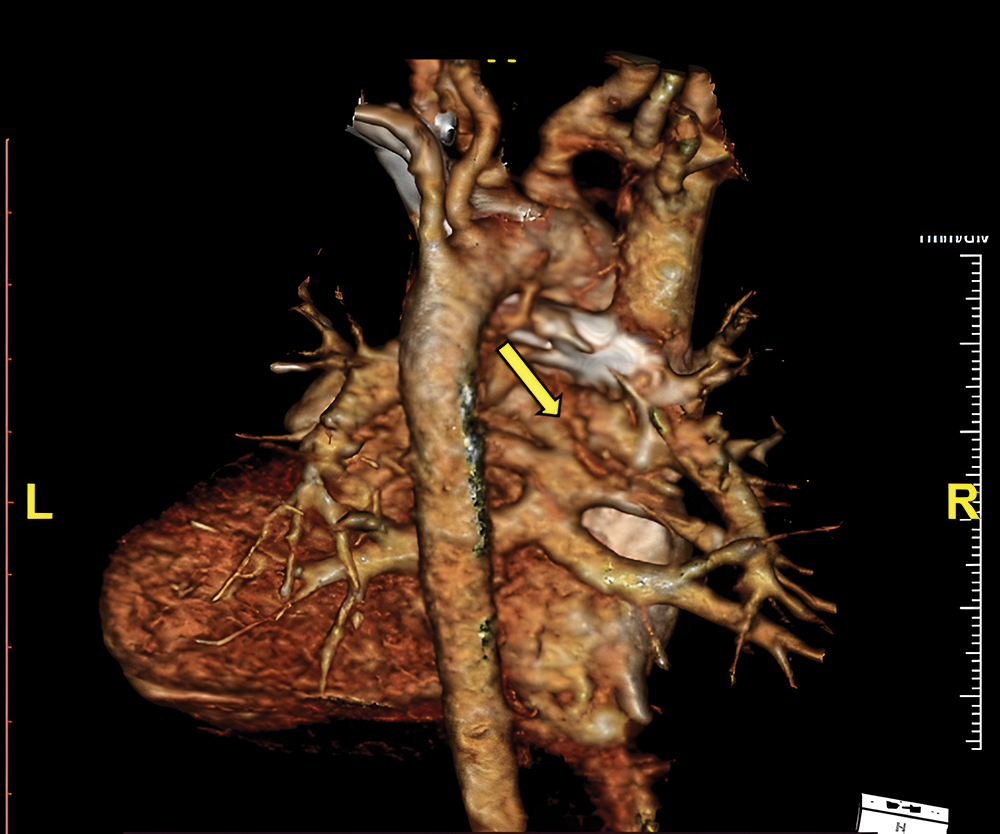

Her clinical characteristics, chest radiograph, and bedside transthoracic echocardiography (Figs. 2A–2C) supported the diagnosis of tetralogy of Fallot (TOF). Additional lesions were also identified, consisting of mixed-type TAPVC with the end of the pulmonary veins connected to the superior vena cava (SVC) and right atrial junction, and a large secundum atrial septal defect (ASD) (Figs. 3A and 3B). The preoperative pressure gradient across the right ventricular outflow tract (RVOT) was 58 mmHg. LA chamber was 17 mm in diameter (z-score < −3 for BSA 0.489 m2), and LV chamber during diastole was 21 mm (z-score < −3 for BSA 0.489 m2) [4]. Additionally, a multi-slice CT scan confirmed the diagnosis of TOF with mixed TAPVC (Fig. 4). The McGoon ratio of this patient was 1.802, which was deemed acceptable for TOF repair. No diagnostic challenges were identified. The patient was then scheduled for total corrective repair for the TAPVC, right ventricular outflow tract and chamber defects reconstruction in TOF, and creation of patent foramen ovale.

Figure 4: Preoperative MSCT shows supra cardiac connection where the two pulmonary veins from each lung converge to common pulmonary vein before joining the superior vena cava (arrow)